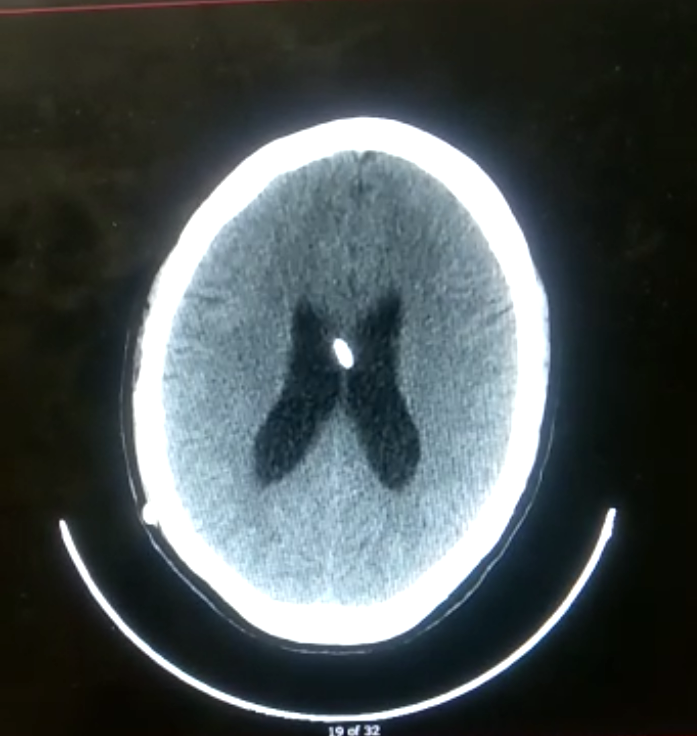

Simple contrast-enhanced MRI of the skull March 17, 2022: Tumor of the posterior fossa located adjacent to the posterior face of the brain stem and extending caudally through the foramen magnum is hypodense on T1 and hyperintense on T2 in a heterogeneous manner on pulse sequences T1 with gadolinium shows heterogeneous enhancement, measuring 67x25x29mm. • Simple skull CT scan: March 22, 2022: tumor at the level of the IV ventricle, probable ependymoma, ventriculostomy valve. Posterior fossa elements of adequate volume and density. A space-occupying process of heterogeneous density, mixed, with solid, cystic areas and calcifications, located in the IV ventricle, measures 27 x 20mm, is identified. ●Chest x-ray: 03/11/22. Shortened, slightly rotated, preserved lung volume, without presence of consolidation or effusion. • Electrocardiogram: 03/14: at 25/10 mm/mv, with 86 bpm, sinus rhythm, T-wave inversion in AVR, v1, v2. No presence of ischemia or necrosis lesion (Figure 1 & 3).

Figure 1 Brain image showing hydrocephalus, after placement of the ventriculoperitoneal catheter.